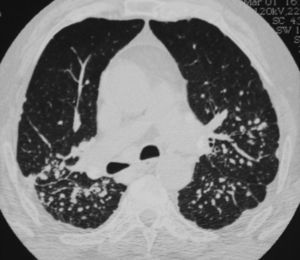

Clinical PresentationA 70-year-old retired worker from a granite quarry was diagnosed at age 43 with seropositive RA with involvement of hands, feet, knees and hips. He subsequently developed pneumoconiosis and pulmonary rheumatoid nodules (Fig. 1), being diagnosed as Caplan's syndrome. During his progression, he was treated with NSAIDs, corticosteroids, gold salts, cyclosporine and methotrexate. Despite this, the patient developed structural damage in the hands, feet and hips, requiring placement of prosthesis in both hips at 51 and 54 years of age, respectively. In recent years, his disease remained stable, treated with methotrexate 10mg weekly and low doses of glucocorticoids, with no evidence of inflammatory joint activity. He presented ‘gooseneck’ deformities in all fingers and rheumatoid nodules on the elbows. 12 months ago he suddenly developed fever and pain in his right groin, with subsequent septic shock, demonstrating an infection of the right hip by Salmonella spp. Methotrexate and glucocorticoids were suspended, and he was treated with prolonged antibiotic therapy and partial replacement of the prosthesis. Laboratory tests evidenced persistent neutropenia, despite the withdrawal of myelotoxic drugs and the improvement of sepsis, reaching 0neutrophils/mm3. Retrospectively, when reviewing the numbers of neutrophils, he had low counts a year earlier, between 1800 and 1000/mm3. The rest of the blood count and biochemistry were normal. The ESR was 80mm/h and CRP 111mg/l. He maintained high levels of rheumatoid factor (6930U/ml) and anti-CCP (300U/ml) and also had polyclonal hypergammaglobulinemia. Antinuclear antibodies and extractable nuclear antigens were negative and complement levels were within normal values. HLA typing showed that he carried the haplotype DRB1*0404 (DR4) and mild splenomegaly was detected (13.7cm) on abdominal computed tomography.